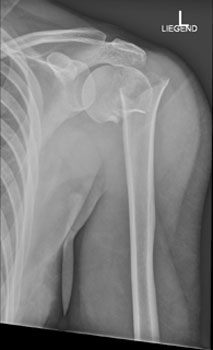

Die Röntgenaufnahme der Schulter in zwei Ebenen ist die Untersuchung der Wahl zur Beurteilung der Knochenstrukturen und der Gelenkstellung.

Hier sehen Sie die Aufnahmen im vorliegenden Fall:

Schulter ap

Schulter nach Neer